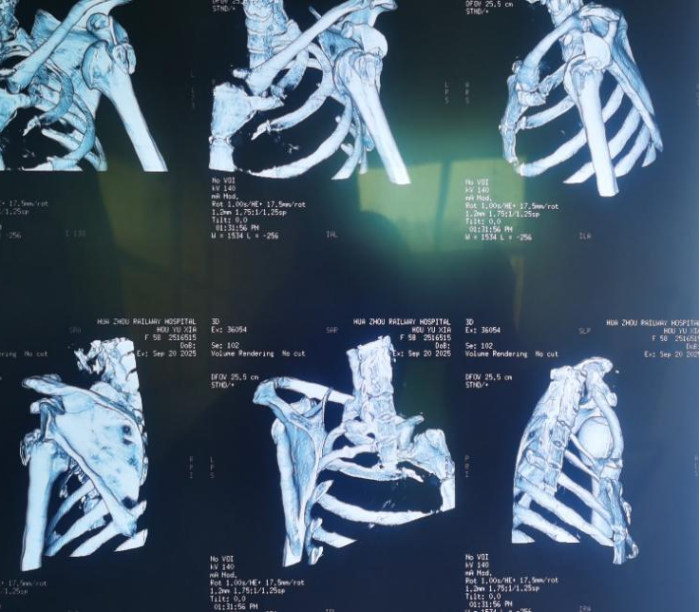

质控科组织术前多学科讨论